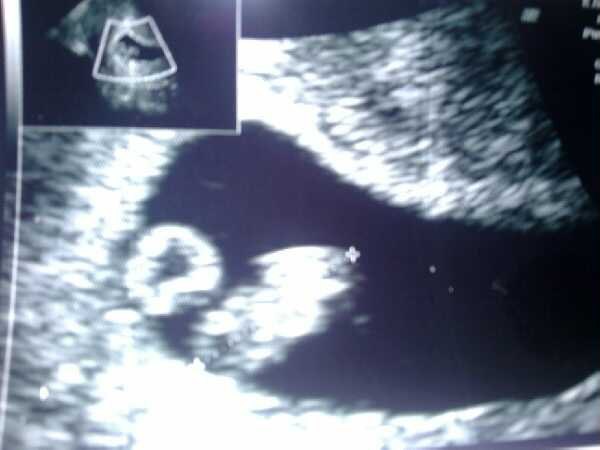

Ved jeg Ikke endnu (; Så den overraskelse har jeg stadig til gode

MEn glæd dig til din første scanning det er en fantastisk oplevelse

Og Stort tillykke med graviditeten ... Det er en skøn følelser når der er liv derinde